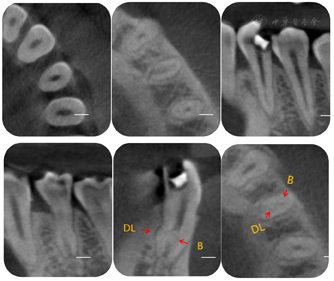

34远中邻牙合面可见白色暂封材料,部分脱落松动,叩痛(±),不松动,牙龈龈缘稍红肿,无窦道口,牙髓活力测试:无反应,咬合:无异常动度。见图1。根尖片示:34牙冠远中邻合面高密度充填影像达髓腔;髓腔高大,髓室底低,根分叉向根方移位,牙根中下1/3膨大,根管影像不清,根周膜影像不清。见图2A。CBCT示:⑴横断面:髓腔高大,髓室底低,牙根下段根管形态复杂,中下1/3牙根横截面呈C形(见图3A、3B);⑵近远中观:颊侧通路影像清晰,舌侧通路影像不清,髓室底距颊尖约:14.0mm,髓室底距CEJ约:7.6mm(见图3C、3D),测量牛牙症指数(taurodontic index,TI),AB:15mm、AC:7.6mm,AB / AC x100%= 50.7%,为重度牛牙症(见图5);⑶颊舌侧观:舌侧通路弯曲明显,呈"S"形,根尖1/3根管影像不清(见图3E)。

诊断证据:⑴根据主诉和现病史中疼痛性质和特点,临床检查中牙髓活力测试:无反应,影像学检查(X线片和CBCT)示:根尖周未见明显病变,诊断34慢性牙髓炎。⑵左下颌第一前磨牙CBCT近远中向TI测量,AB:15mm、AC:7.6mm,AB / AC x100%= 50.7%诊断为重度牛牙症(见图5)。⑶CBCT横断面示:34牙根中下1/3牙根横截面呈C形(见图3B),诊断为34 C形根管。

治疗过程:34去除暂封材料及棉球,洞壁见大量腐质,颊侧及舌侧的髓室顶未完全揭除(见图7A);去净腐质,玻璃离子制作假壁,上橡皮障,揭净髓室顶,显微镜下见髓腔狭窄,髓室底深。依据术前CBCT测量数据:髓室底距颊尖:14.0mm,髓室底距釉质牙本质界CEJ:6.5mm,在显微镜下,使用超声ET20去除牙本质领,修整、扩大髓室壁,建立直线通路。见髓室底有钙化物,同时去除髓室底钙化物,充分暴露髓室底,DG16仅探及颊侧通路,C+疏通,扩大至15#。在CBCT上对远舌通路进行定位,远舌通路位于颊侧通路远中舌侧约2.0mm(见图3F),显微镜下,ET25逐层去除根管口牙本质领,充分暴露远舌通路根管口,根管弯曲细小,伴有弥漫性钙化,依次使用6#、8#、10# C锉,尖端2mm预弯,结合EDTA凝胶逐号疏通根管,1%NaClO大量冲洗,回挫,电测根管长度:B=21.0mm,DL=19.0mm,镍钛预备根管,B:25# 6%,DL:25# 4%。试主尖,根尖片发现根管有遗漏(见图2B)。再次结合CBCT对近舌通路进行定位CBCT颊舌观:近舌牙根弯曲,根管影像不清(见图6B);横断面:近舌通路根管口位于颊侧通路远中舌侧1.5mm,远舌通路近中颊侧约1.0mm,近舌通路根管口牙本质领较厚(见图6A),显微镜下,ET25少量缓慢逐层去除1~2mm钙化物及牙本质领,小号锉反复探查,探及近舌通路根管口;疏通方法同远舌通路,电测根管长度:ML=19.0mm,EDDY尖结合1%NaClO声波活化荡洗,试主尖,X线片示:到达工作长度(见图2C),根管内封入Ca (OH )2糊剂,玻璃离子暂封。2周后复诊,患牙未诉不适,iRoot sp单尖充填3通路,髓腔热牙胶回填,完成根管治疗。术后拍摄X线片显示,根管充填恰填(见图2D)。

牛牙症患牙形态改变大,拉长的髓腔、多样的根管形态,对临床医生来说无论是从诊断还是治疗都是一种挑战。目前国内大多数地区仍然通过传统X线片检查诊断牛牙症,但是,许多因素如根管的变异、不同的拍片投射角度、解剖关系的重叠等都会干扰医生的判断,这给牛牙症的正确诊断和治疗带来了困难[12]。而对于C形根管是在牙根横断面呈C形,X线片不能观测牙齿的横断面情况,临床上,X线片辨别只能根据C形根管的牙根和根管走向来间接判断。本例患牙术前X线片仅发现患牙髓腔高大,髓室底低,根分叉向根方移位,牙根中下1/3膨大,根管影像不清等特征,并不能确诊患者是否存在牛牙症和C形根管。随即我们术前拍摄了CBCT,发现患牙髓室高度增加,髓底向根尖方向移位,牙根较短小,中下1/3牙根横截面呈C形,舌侧牙根弯曲明显、呈"S"形,根尖1/3根管影像不清,同时在CBCT近远中向测得TI= 0. 57,诊断为重度牛牙症伴C形根管。Darw azeh[13]等报道高达26. 7%的牛牙症患牙存在不同程度的髓石及根管钙化,伴随其特殊的髓腔形态给根管治疗造成很大的困难[14]。发生于前磨牙的C形根管系统形态复杂,存在较大变异,容易遗漏根管,这为治疗增加了难度[15]。本例牛牙症患牙舌侧通路根管口牙本质领较厚,根管细小弯曲,并伴有不同程度的钙化,在治疗过程中发现舌侧根管口难以寻及。因此,在治疗过程中我们也反复借助了CBCT三维导航作用,准确定位远舌根管口和近舌根管口的位置,并从多个角度更准确直观地反映根管走向、弯曲程度、钙化长度、位置及变化,为弯曲、钙化根管的治疗提供了可靠的信息。通过本病例我们建议在复杂根管治疗过程中要充分利用和分析CBCT,结合根管显微镜的照明和放大功能准确定位钙化根管口,采用超声设备精细去除牙本质领和钙化物。同时,配合使用小号C锉(尖端2mm预弯)和EDTA根管凝胶疏通根管,疏通时特别注重回锉和冲洗液的大量冲洗,避免台阶、侧穿及根管偏移等不良并发症的发生。预备舌侧弯曲根管使用可预弯的记忆型镍钛锉,防止出现器械分离。对于弯曲根管的化学预备,国外学者[16]发现EDDY具有较好的清洁作用,本病例我们选用了EDDY声波工作尖越过根管弯曲部位,到达距根尖1mm进行荡洗,通过这些措施提高了牛牙症根管治疗的成功率。在病例中我们也学到了:通过认真细致地临床检查,利用X线片、CBCT和显微镜观察对根管形态进行准确的判断,选择合适的器械,临床医生细致耐心的操作以及病人的配合,是治疗成功的重要因素。